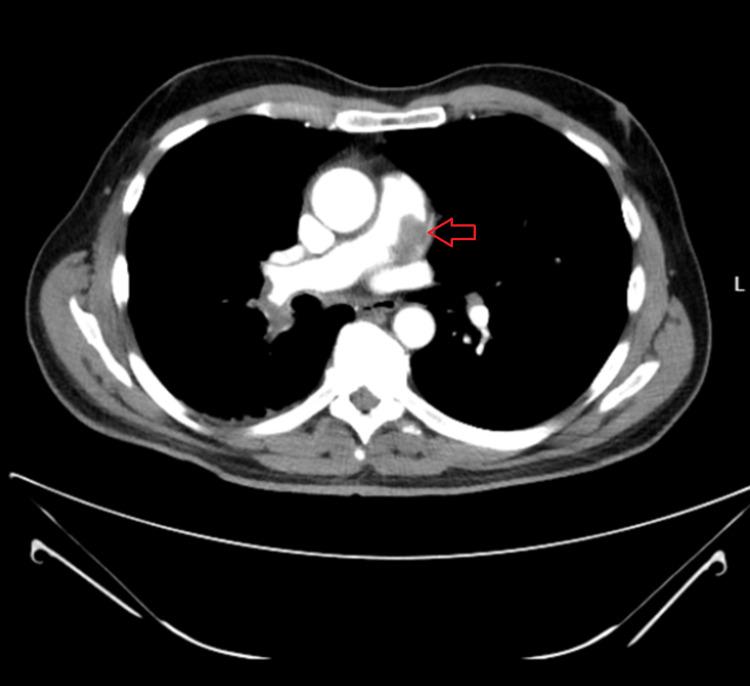

Leiomyosarcoma of the pulmonary artery is a rare but potentially fatal disease. Due to its rarity, the treatment algorithm is not well-established. While there may be a role for both chemotherapy and radiotherapy, surgical management is the most definitive method. Unfortunately, when the disease process is advanced, surgery may not be curative. However, it may still be a palliative treatment option. In this case report, we present a patient who suffered from respiratory symptoms that were initially attributed to pulmonary embolism (PE). However, upon the diagnosis of pulmonary artery leiomyosarcoma (PAL), surgery intervention was undertaken and resulted in an improved quality of life for the patient.

肺动脉平滑肌肉瘤是一种罕见但可能致命的疾病。由于其罕见性,治疗方案尚未完全确立。虽然化疗和放疗可能都有一定作用,但手术治疗是最具决定性的方法。不幸的是,当疾病进展到晚期时,手术可能无法治愈。然而,它仍然可能是一种姑息性治疗选择。在本病例报告中,我们介绍了一名患者,其最初出现的呼吸道症状被归因于肺栓塞(PE)。然而,在诊断为肺动脉平滑肌肉瘤(PAL)后,进行了手术干预,患者的生活质量得到了改善。